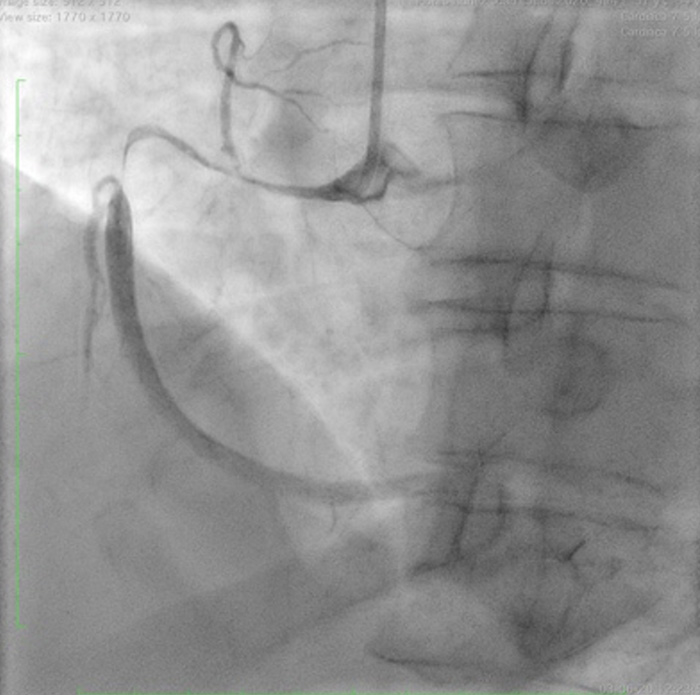

A 59-year-old man. Arterial hypertension and smoker. Consultation due to oppressive chest pain. Electrocardiogram: ST elevation in the inferior and anterior walls. Coronary angiography was performed.An image is worth a 1,000 words: participate in the quiz below to tell us what you see in this image!

• Ali Nazmi Calik 22 Apr 2023

• anil sarica 23 Apr 2023

Discection

• Soham Chaudhari 29 Apr 2023

SCAD TYPE 2